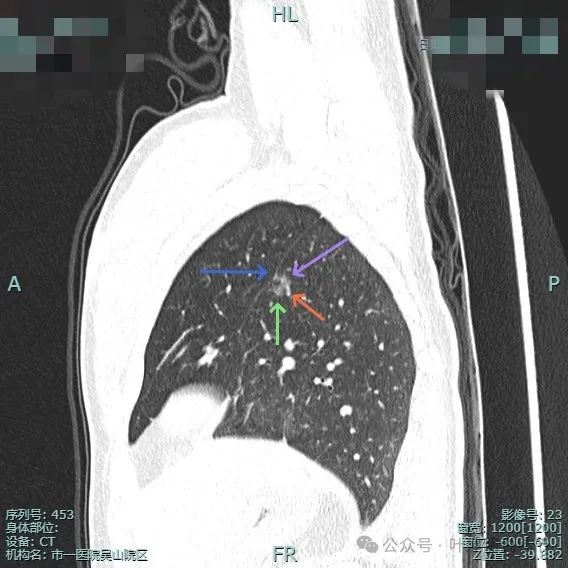

边缘毛糙,血管进入,灶内密度显得杂乱。

有扭曲的血管进入血管,表面有凹陷与分叶。

密度不太纯,表面不平,血管有异常增粗。

胸膜有轻微牵拉,表面不平,多处微小血管进入,整体密度显得不匀。

血管征明显、灶内小空泡征、胸膜牵拉、边缘细毛刺征。

整体看上去密度不均、边缘不平、灶内空泡征以及细毛刺征均明显。